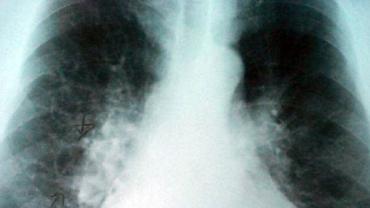

La EPOC es la cuarta causa de mortalidad en España. Entre un 50 y un 80 por ciento de los pacientes utiliza incorrectamente los inhaladores para la administración de medicamentos